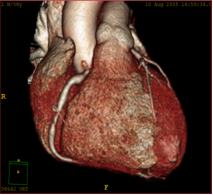

This latest 64 slice CT machine has a special role in Cardiac Angiography, since this investigation has been found to be a viable alternative to catheter angiography. Cardiac coronary Angiography has been found to be highly sensitive and specific in diagnosing coronary artery stenosis, stenosis in coronary stents and occluded coronary bypass grafts. The added advantage of Cardiac CT angiography is that it is completely non invasive, unlike catheter angiography. Also it is the modality to detect and characterize silent non-obstructive atherosclerotic plaques, which may be associated with adverse outcome and cannot be picked up on catheter angiography

Mid RCA Stenosis